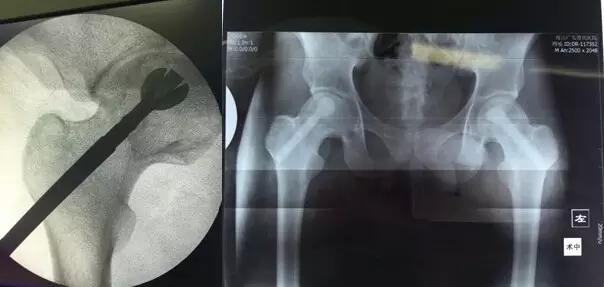

3月29日,舟山廣安醫(yī)院危立軍副院長(zhǎng)為一名29歲的雙側(cè)股骨頭早期壞死患者成功實(shí)施了股骨頭壞死減壓、病灶清除、可注射人工骨植入術(shù)。這是當(dāng)前國(guó)際上在治療此類疾病的最先進(jìn)的微創(chuàng)手術(shù)技術(shù)。該項(xiàng)技術(shù)可以有效阻止股骨進(jìn)一步頭壞死而導(dǎo)致關(guān)節(jié)軟骨面塌陷,通過(guò)再造創(chuàng)面誘導(dǎo)骨再生、成骨而達(dá)到治愈目的。

治療股骨頭壞死的關(guān)鍵是終止病變進(jìn)展,在股骨頭壞死的早期階段,保留患者自身髖關(guān)節(jié)具有很高的臨床和社會(huì)價(jià)值。使之有可能往良性的軌道上發(fā)展。廣安醫(yī)院開(kāi)展的“股骨頭壞死減壓、病灶清除、可注射人工骨植入術(shù)”,在保護(hù)已發(fā)生的壞死骨基礎(chǔ)上,同時(shí)通過(guò)生物學(xué)反應(yīng)促進(jìn)骨再生和病變組織修復(fù),有效恢復(fù)承重能力,防止股骨頭變形塌陷。該技術(shù)手術(shù)切口長(zhǎng)約1-2厘米,創(chuàng)傷小,費(fèi)用低,恢復(fù)快,術(shù)后第二天即可出院,門診治療。